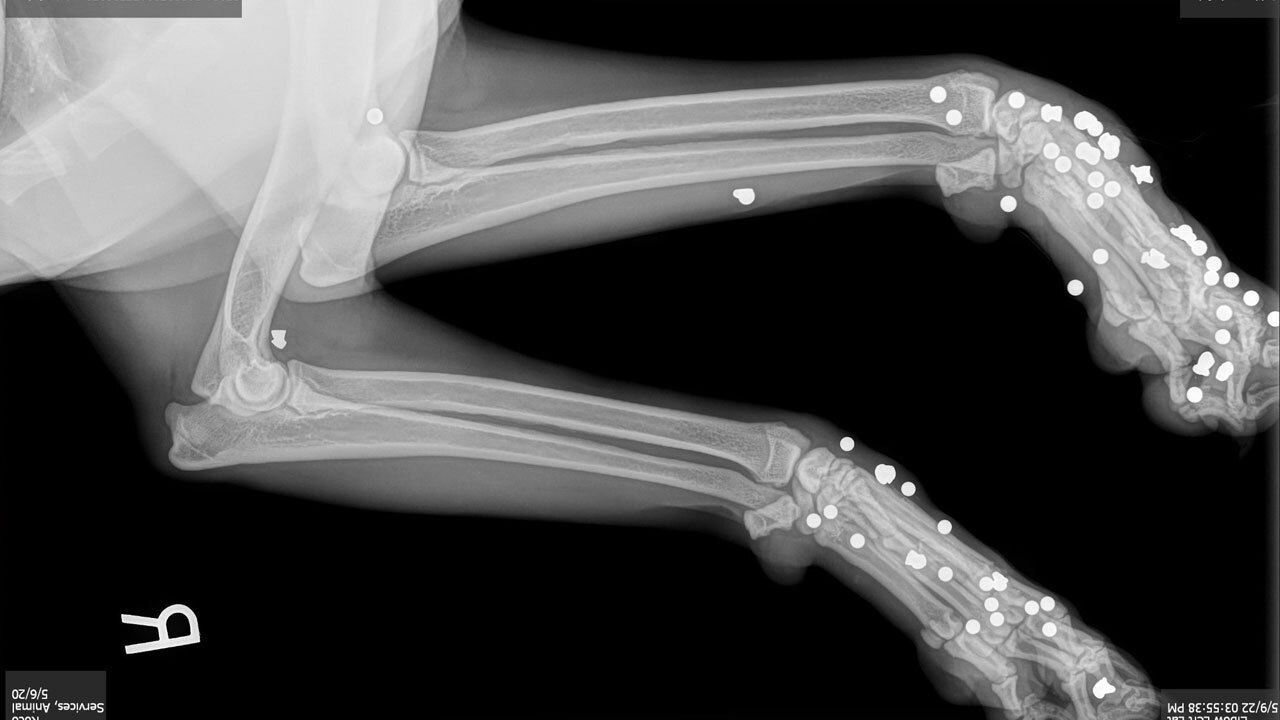

Three days later, both dogs were sent to a local veterinarian for x-rays.

In the first dog's x-rays, according to HCSO, approximately 61 BBs and 19 lead pellets were spotted throughout the dog's legs, torso and head. They said approximately 71BBs and 22 lead pellets were identified on the second dog's x-rays.